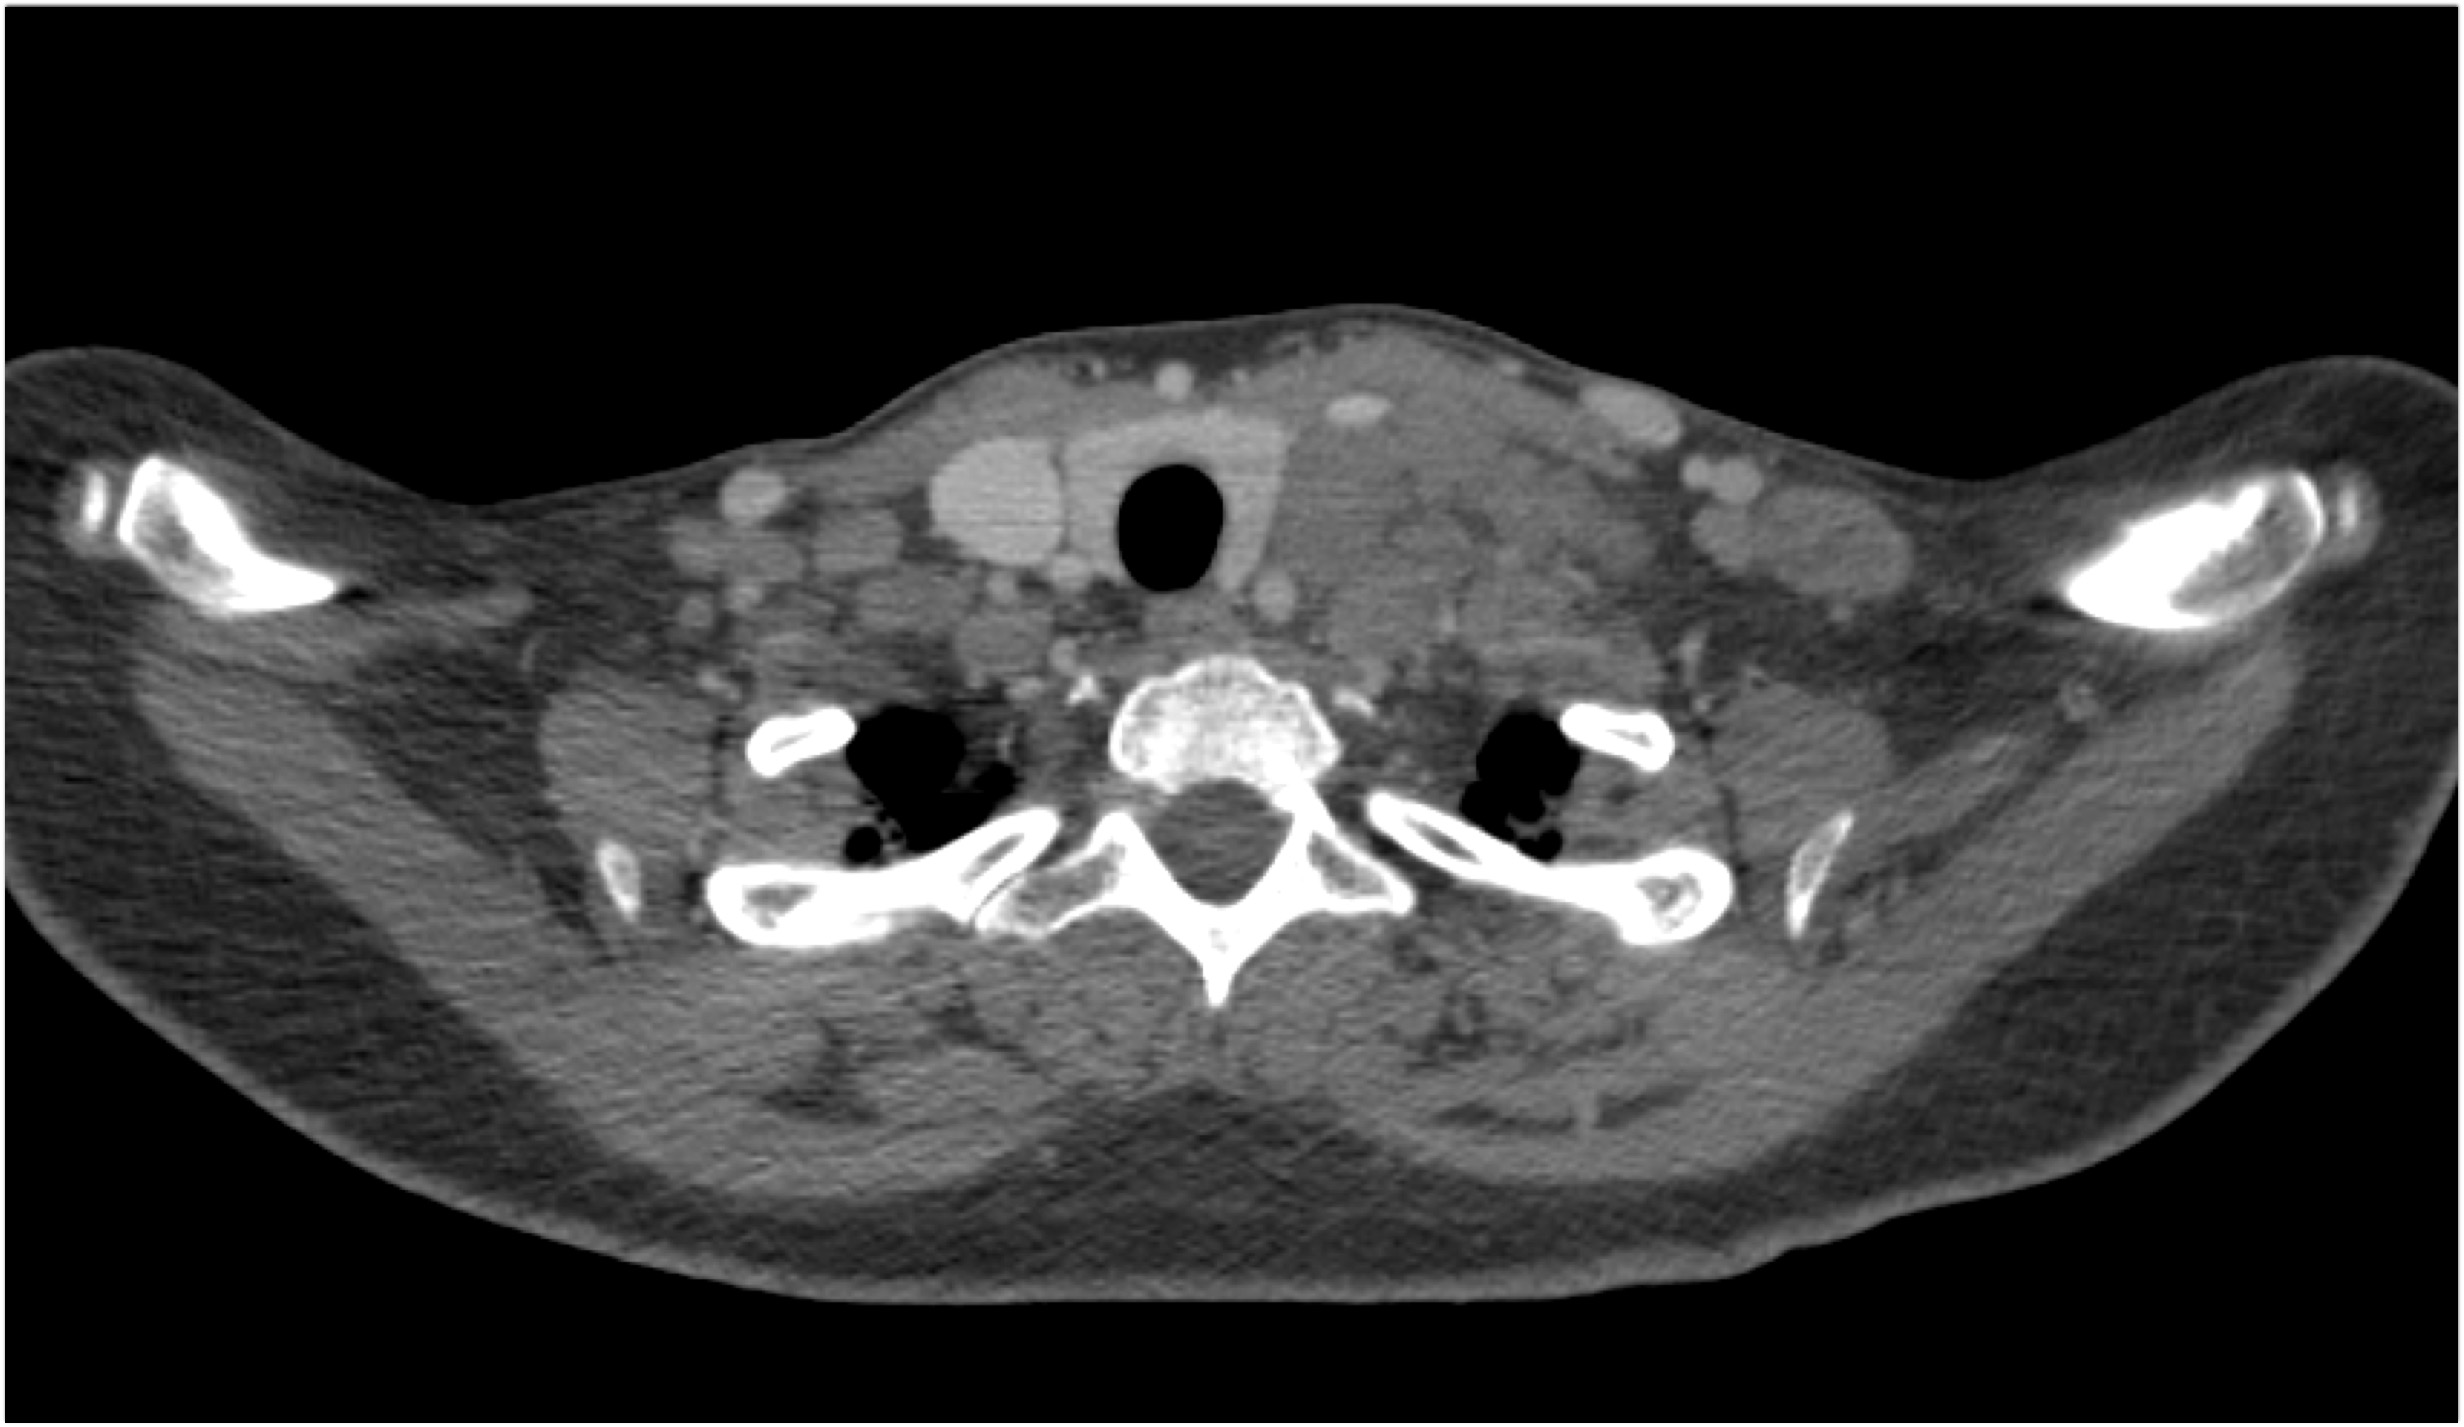

3) The most likely diagnosis in this case is?

lung cancer

lymphoma

pulmonary artery aneurysm

sarcoidosis